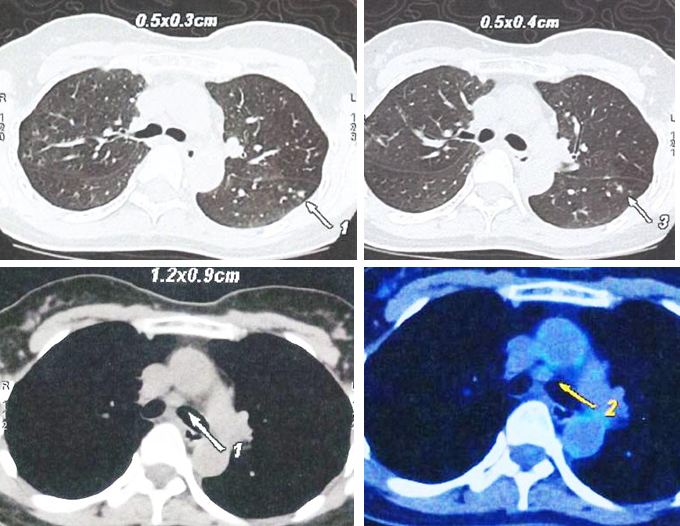

3. Whole body PET-CT scan. This was done on 17 September 2022.

Two small hypermetabolic nodules at 12 o’clock and 1 o’clock positions of left breast are consistent with biopsy proven malignancy.

A group of several minimally FDG avid tiny irregular nodules in left lung are more likely inflammatory than neoplastic judging from their distribution.

Small hypermetabolic focus in right corn of uterine cavity can be inflammatory change, but malignancy is not excluded. Gynecological evaluation is recommended.

Otherwise, no metabolic evidence of distant metastasis.

My question to that argument is: With that extra information, what can you do about the real problem? For example, PET scan showed there are nodules in the lungs and a “hot spot” in the uterine cavity. So what did the surgeon do about this “finding or knowledge”? The surgeon did nothing since her/his job is only to cut off the breast! Also, how sure are you that these “extra information” can really save your life?